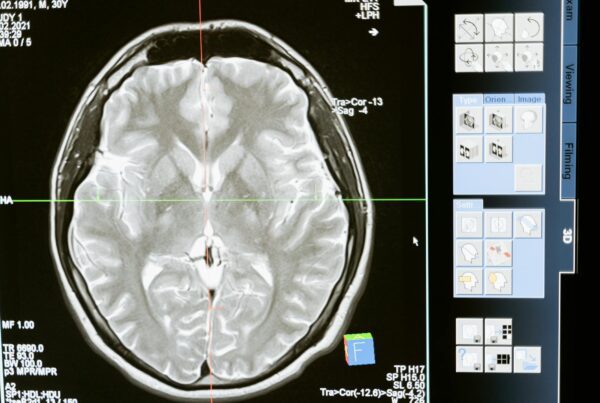

- Doenças Neurodegenerativas: Desenvolvimento de protocolos de RM habilitados por IA para melhorar a precisão diagnóstica e o monitoramento longitudinal de condições como Alzheimer e Parkinson. O objetivo é detectar alterações sutis antes que os sintomas clínicos se manifestem.

Dois centros de inovação sustentam a parceria. Um deles concentra-se em imagem por RM de ultra-alto campo para condições neurológicas, explorando o potencial de campos magnéticos mais intensos para revelar detalhes anatômicos e funcionais antes invisíveis. O segundo centro apoia a integração clínica de PET/CT e PET/RM de corpo inteiro, incluindo teranósticos e imagem combinada anatômico-metabólica para oncologia.